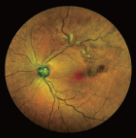

ICGA主要用于觀察脈絡(luò)膜的血管結(jié)構(gòu)和循環(huán)特點,揭示脈絡(luò)膜循環(huán)的細(xì)節(jié),是目前PCV診斷的“金標(biāo)淮“。且由于吲哚青綠染料具有與熒光素鈉不同的特性,所以能更加直觀地了解脈絡(luò)膜血管循環(huán)狀態(tài),可彌補FFA檢查看不清脈絡(luò)膜循環(huán)的不足,在某些特殊情況下可協(xié)助FFA對視網(wǎng)膜血管性疾病診斷作出補充。

ICGA影像